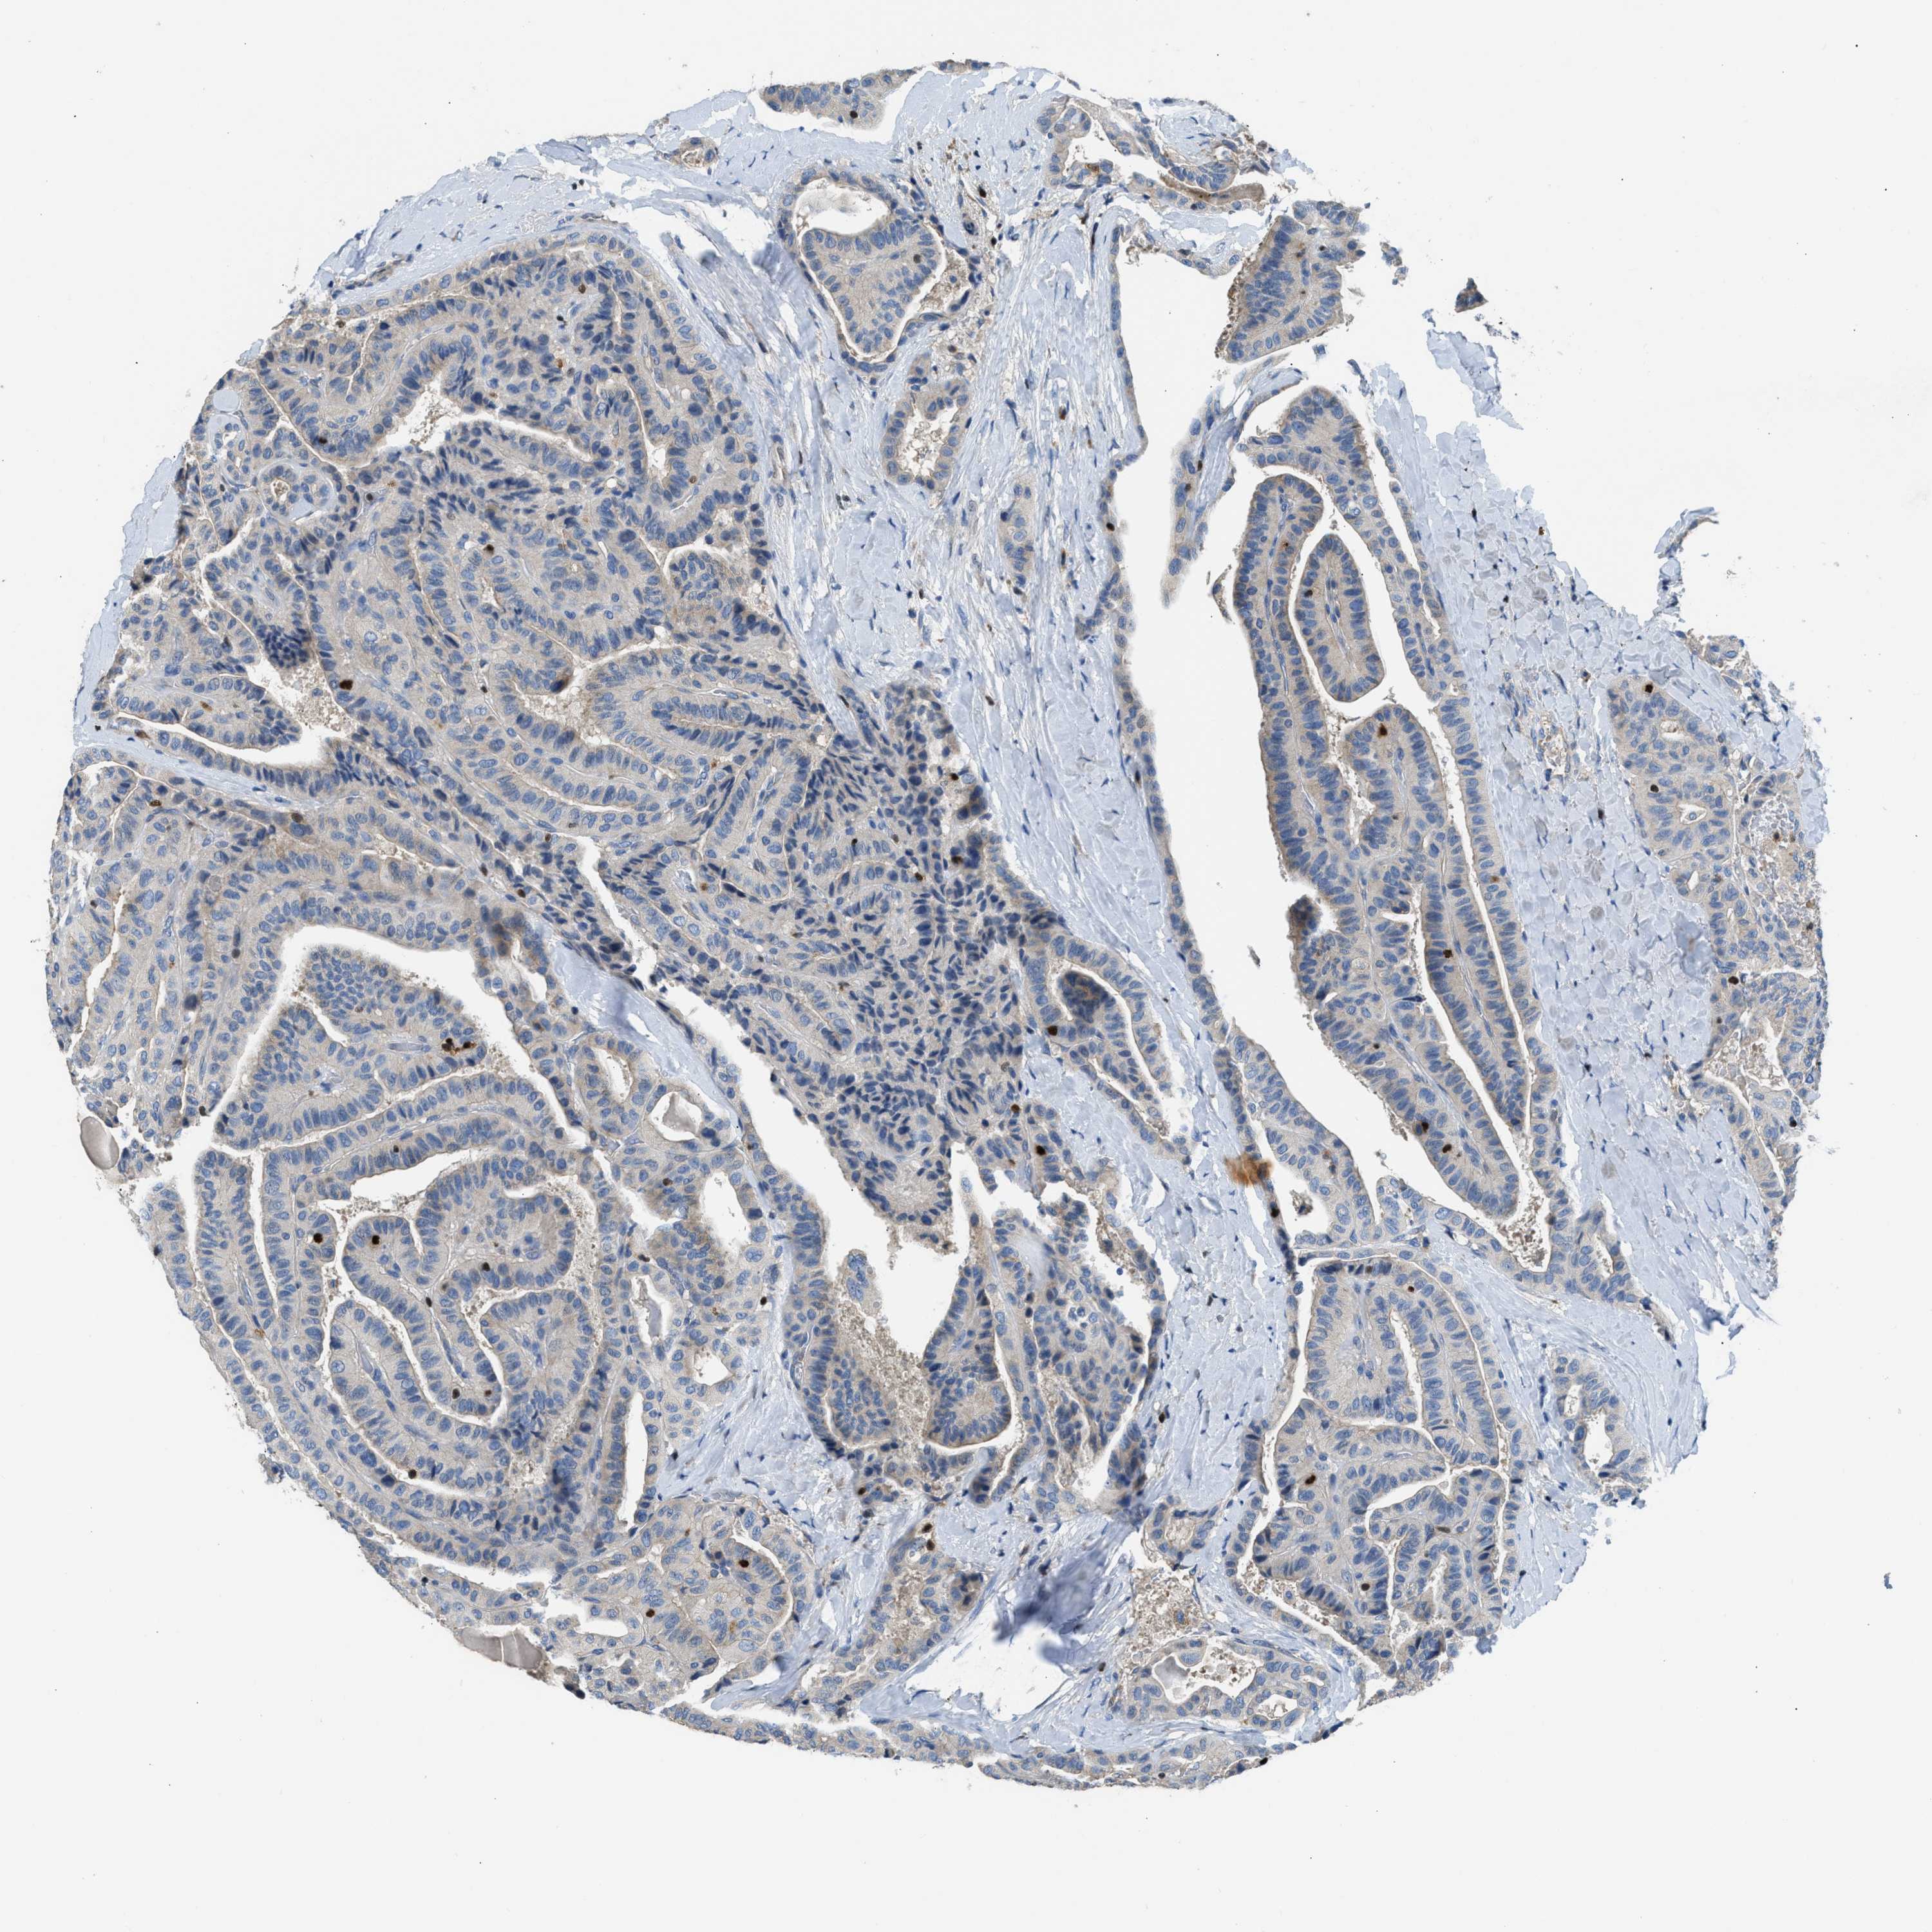

THYROID CANCER - Protein expressioni

A mouse-over function shows sample information and annotation data. Click on an image to view it in a full screen mode. Samples can be filtered based on level of antibody staining by selecting one or several of the following categories: high, medium, low and not detected. The assay and annotation is described here.

Note that samples used for immunohistochemistry by the Human Protein Atlas do not correspond to samples in the TCGA dataset.

Antibody stainingi

Antibody staining in the annotated cell types in the current human tissue is reported as not detected, low, medium, or high, based on conventional immunohistochemistry profiling in selected tissues. This score is based on the combination of the staining intensity and fraction of stained cells.

Each image is clickable and will lead to virtual microscopy that enables deeper exploration of all samples and also displays staining intensity scores, fraction scores and subcellular localization as well as patient and tissue information for each sample.

Antibody HPA018322

Staining

High

Medium

Low

Not detected

Intensity

Strong

Moderate

Weak

Negative

Quantity

>75%

75%-25%

<25%

None

Location

Nuclear

Cytoplasmic/membranous

Cytoplasmic/membranous,nuclear

Papillary adenocarcinoma, NOS

Follicular adenoma carcinoma, NOS